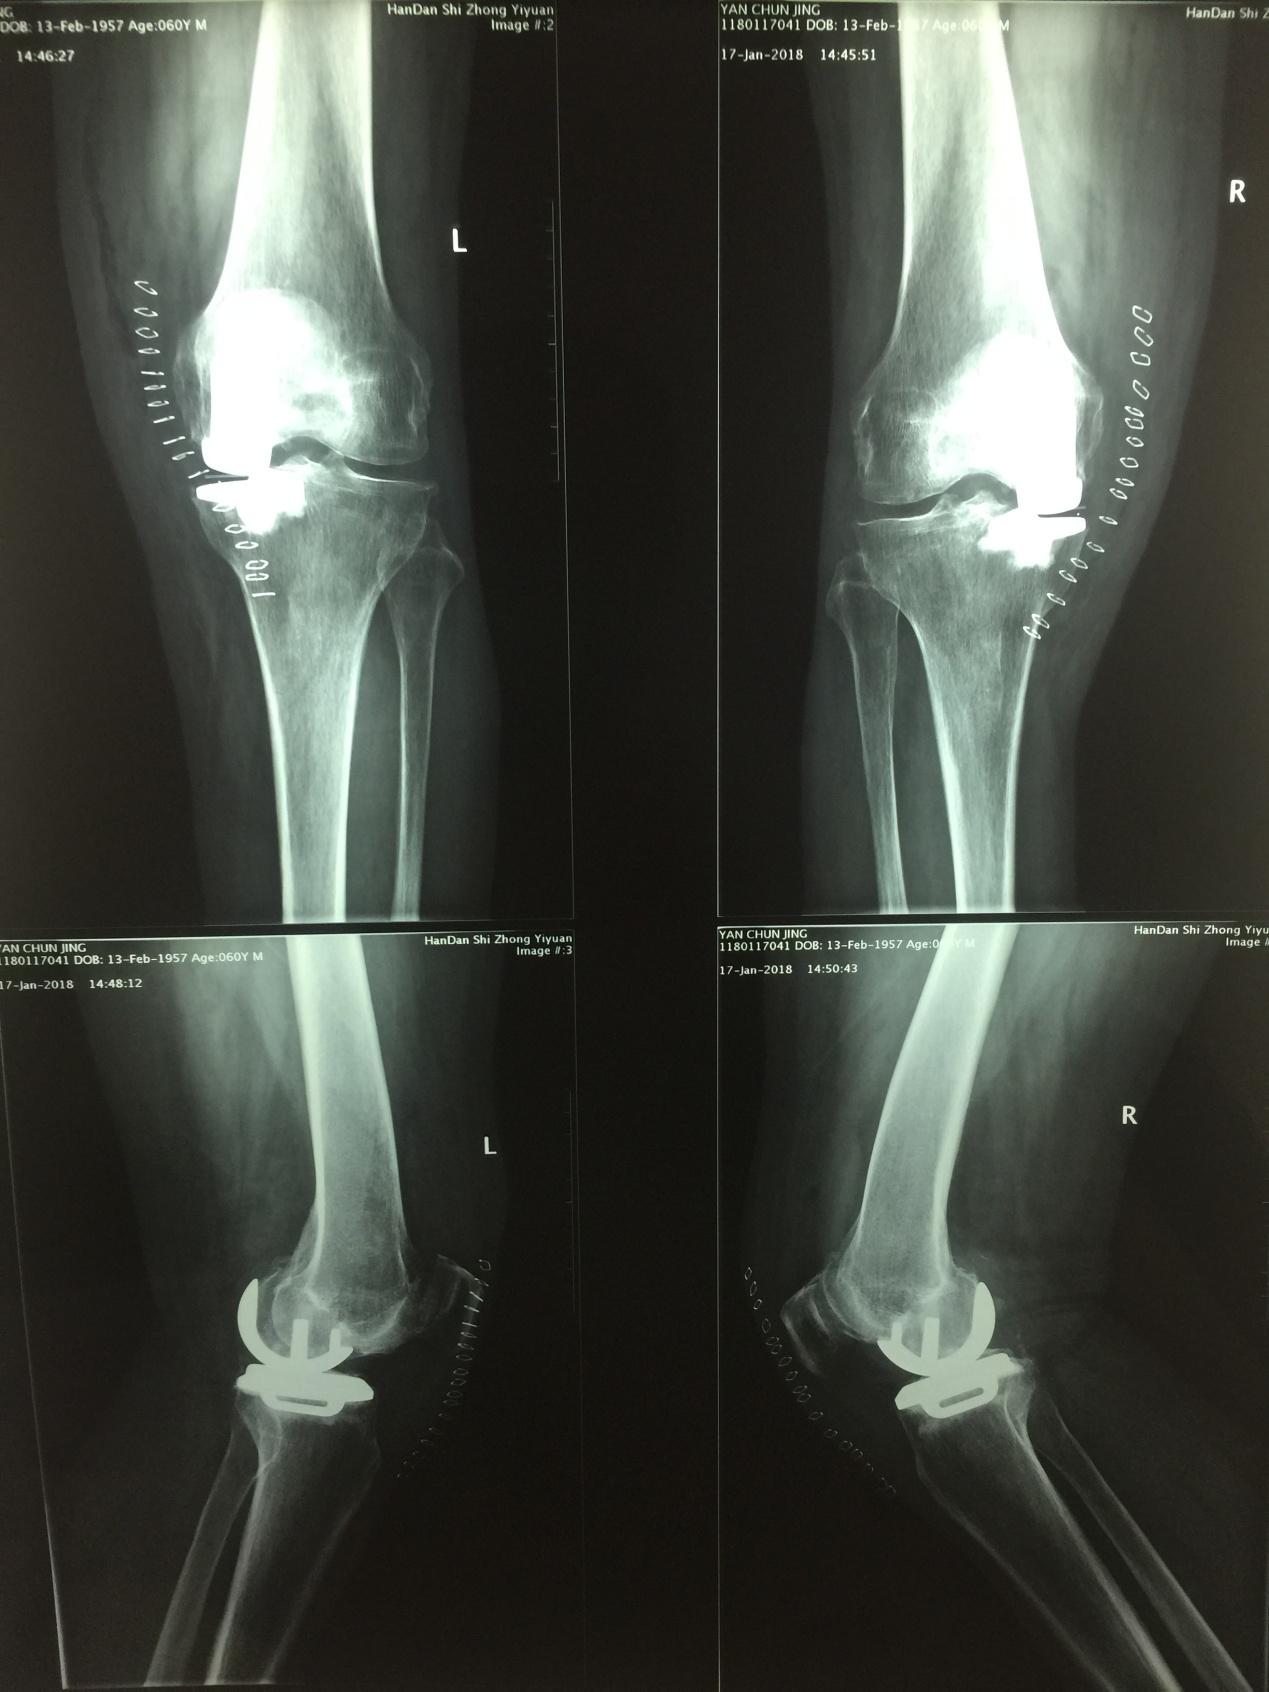

随着人口老龄化,膝关节骨关节炎的发病率逐年增高,膝关节骨关节炎的治疗方法很多,探索膝关节骨关节炎的阶梯化治疗成为必然。1月16日下午,我院骨六科主任甄红军,带领蒿俊行主治医师、刘章主治医师,成功完成医院首例一期双膝关节骨关节炎单髁关节置换术。标志我院在膝关节骨关节炎保膝治疗领域又上一个新台阶。 患者闫先生,男,60岁,双膝关节疼痛10余年,关节内翻畸形、活动受限,经口服药物、关节腔注射玻璃酸钠、关节镜清理术后、症状反复发作,影响生活和工作,不能正常行走。来到中医院就诊后,骨六科甄红军主任经科室会诊讨论后认为:患者男性60岁,主要表现为双膝关节内侧疼痛,X线片显示膝关节内侧间室退变严重、外侧关节间室、膝关节交叉韧带和髌股关节良好,决定给患者行双膝关节单髁关节置换手术,手术顺利,术后患者恢复良好。 膝关节单髁置换术:是应用MIS微创技术,不破坏膝关节韧带结构,手术创伤小、术后关节活动度更大、恢复快,病人住院时间短,属于保膝治疗手术。 其适应症:1、膝关节单间室间隙变窄(负重位相),不合并外侧间室和髌骨关节的退变 2、前交叉韧带功能完好 3、年龄在55岁以上,从事轻体力活动的人群 4、膝关节关节内的畸形、屈曲强直畸形角度﹤15。